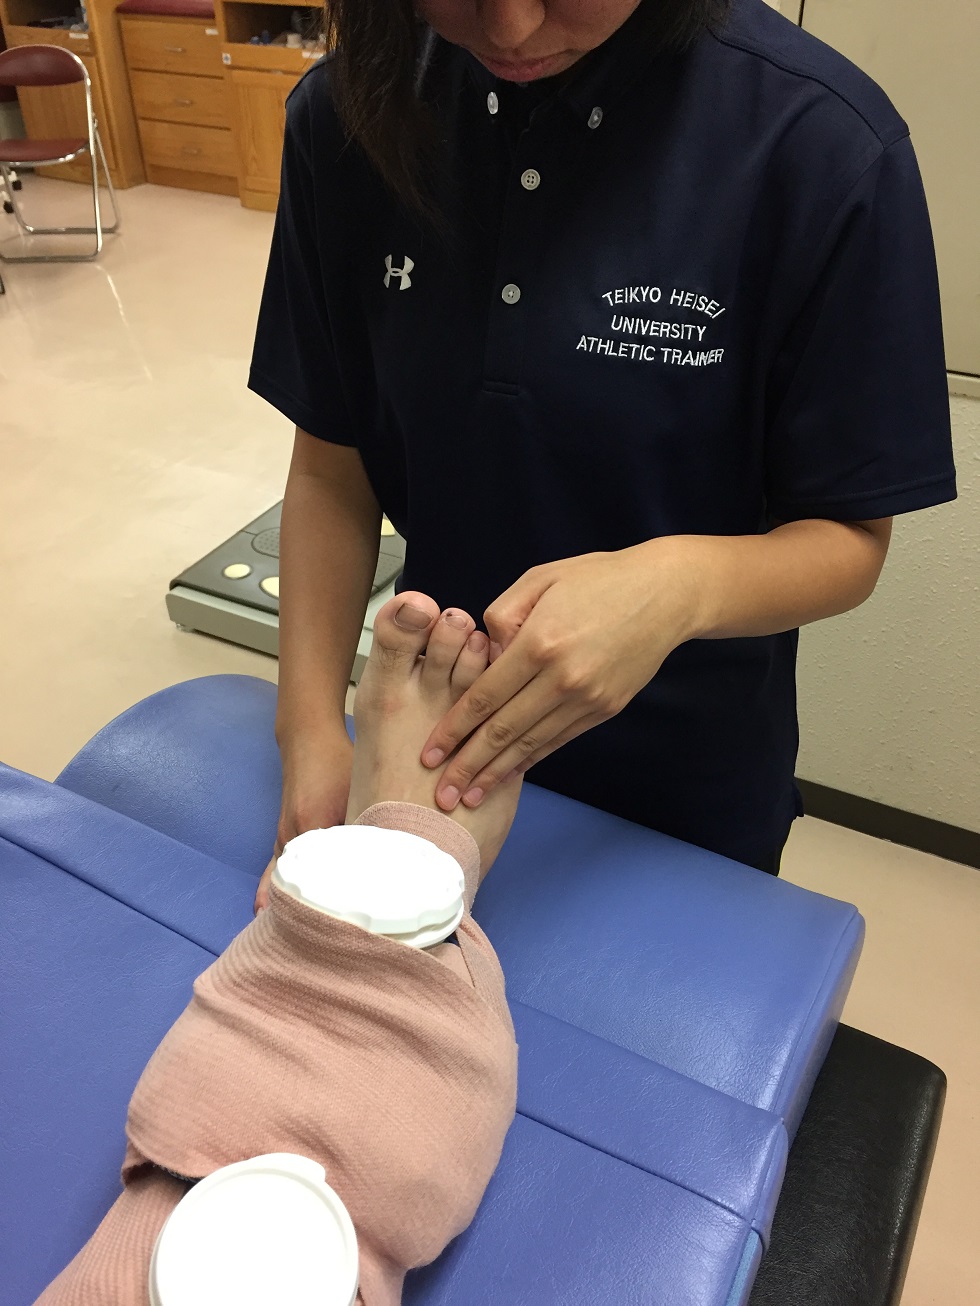

사진 2 발등을 만져 감각 장애 확인

등쪽 동맥 확인